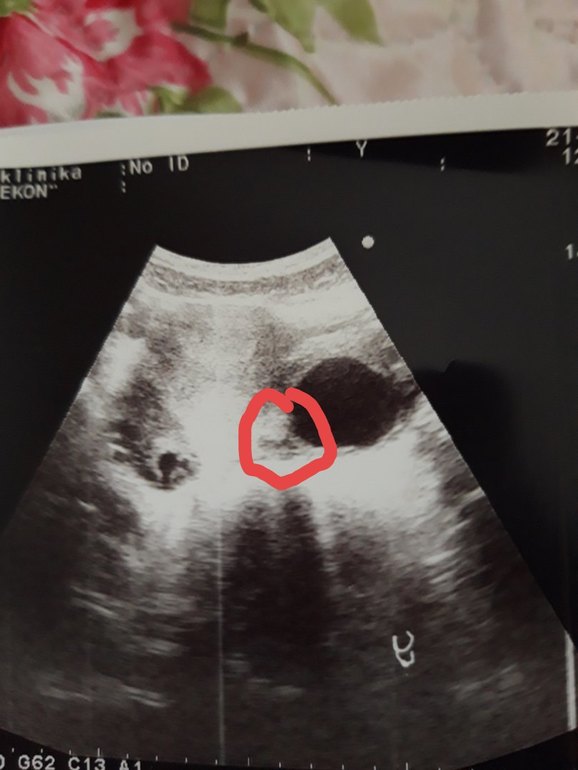

а я что то вижу!

Это фото яичника. Большое черное пятно это киста, вокруг несколько маленьких фолликулов

прежде чем "что-то видеть" посмотрите хотя бы как выглядит беременность малого срока на узи. Киста у вас шикарная. И хорошо что еще маленькая, у меня была 10 сантиметров, я пила с 10 по 25ый дц дюфастон, за 1 такой прогон киста сдулась.

Киста фолликулярная левогояичника 36мм, плодное яйцо не лоцируется, то есть не видит